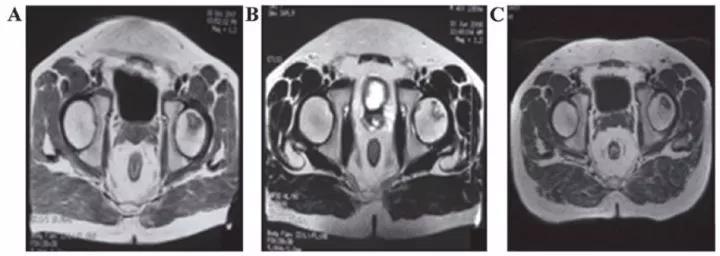

8、泌尿生殖系統(tǒng)疾病

? 不孕不育

子宮內(nèi)膜受損嚴(yán)重,是很多不孕不育女性的噩夢(mèng)?,F(xiàn)在通過間充質(zhì)干細(xì)胞再生技術(shù)修復(fù)子宮內(nèi)膜,可重圓女性的母親夢(mèng)。

南京鼓樓醫(yī)院婦產(chǎn)科胡婭莉教授團(tuán)隊(duì)與中國科學(xué)院遺傳與發(fā)育生物學(xué)研究所戴建武教授團(tuán)隊(duì)聯(lián)手,首次在國際上成功研制出膠原支架復(fù)合間充質(zhì)干細(xì)胞的方法,結(jié)合傳統(tǒng)宮腔鏡技術(shù),實(shí)現(xiàn)了受損子宮內(nèi)膜的功能性修復(fù),幫助3名患者實(shí)現(xiàn)做媽媽的夢(mèng)想。

江蘇鹽城的胡女士在31歲到34歲時(shí),經(jīng)過三次自然流產(chǎn),因?yàn)榱鳟a(chǎn)清宮手術(shù),子宮腔嚴(yán)重粘連。南京鼓樓醫(yī)院利用間充質(zhì)干細(xì)胞8個(gè)月修復(fù)了她的子宮內(nèi)膜,使她成功懷孕,并于2014年7月17日誕下了國內(nèi)第一位“再生醫(yī)學(xué)寶寶”。

南京鼓樓醫(yī)院的間充質(zhì)干細(xì)胞“子宮內(nèi)膜再生”術(shù)已先后讓13位重度子宮腔粘連致不孕的患者成功受孕并分娩,共計(jì)誕生14名健康的“再生醫(yī)學(xué)寶寶”。

? 卵巢早衰

卵巢早衰是指女性40歲之前,因卵巢萎縮而不排卵的現(xiàn)象。目前全世界約有1%的育齡期女性發(fā)生卵巢早衰,這一問題已然成為女性不孕的重要原因。

中國上海交通大學(xué)吳際教授等人從一到兩周大的綠色熒光蛋白轉(zhuǎn)基因小鼠中分離出雌性生殖干細(xì)胞,經(jīng)純化、培養(yǎng)等過程處理后,再移植到卵巢早衰的小鼠體內(nèi)。研究結(jié)果顯示,雌性生殖干細(xì)胞與其他干細(xì)胞一樣具有歸巢作用,歸巢后部分細(xì)胞分化并逐漸發(fā)育為成熟卵母細(xì)胞,從而使卵巢功能恢復(fù)。

南京大學(xué)醫(yī)學(xué)院附屬鼓樓醫(yī)院進(jìn)行的動(dòng)物實(shí)驗(yàn)已經(jīng)證實(shí),臍帶間充質(zhì)干細(xì)胞的復(fù)合膠原移植可以改善大鼠受損傷卵巢的激素水平,恢復(fù)動(dòng)物的發(fā)情行為,縮短發(fā)情周期,有助于卵泡發(fā)育與排卵。研究人員擬募集20位卵巢早衰合并不孕患者,研究臍帶間充質(zhì)干細(xì)胞復(fù)合膠原卵巢移植治療卵巢早衰所致不孕癥的臨床療效,為卵巢早衰的個(gè)體化治療和多中心臨床研究探索合適的方案。